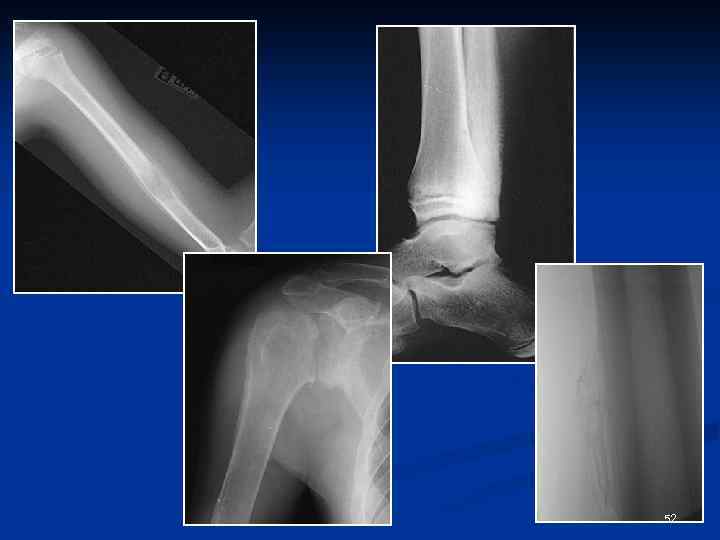

Рентгеновская семиотика изменений надкостницы • Периостоз • Периостит (ответная реакция кости на то или иное раздражение) Виды периоститов: Асептически воспалительные периоститы (при травме) Инфекционно-воспалительные периоститы (при остеомиелите, туберкулезе, сифилисе и др. ) Ирритативно-токсические п. (при опухолях, изменениях в соседних мягких тканях, системных заболеваниях) Функционально-адаптационные Ø Острые периоститы (гнойные, серозные) Ø Хронические (альбуминозный, фиброзный и оссифицирующий) 50

Рисунок периостальных наслоений Линейный (отслоенный) периостит Слоистый (луковичный) периостит Бахромчатый (разорванный) периостит Кружевной (гребневидный) периостит Игольчатый (спикулообразный) периостит Периостит в виде козырька ( «козырек Кодмена» ) Оссифицирующий ассимилированный периостит 51

52